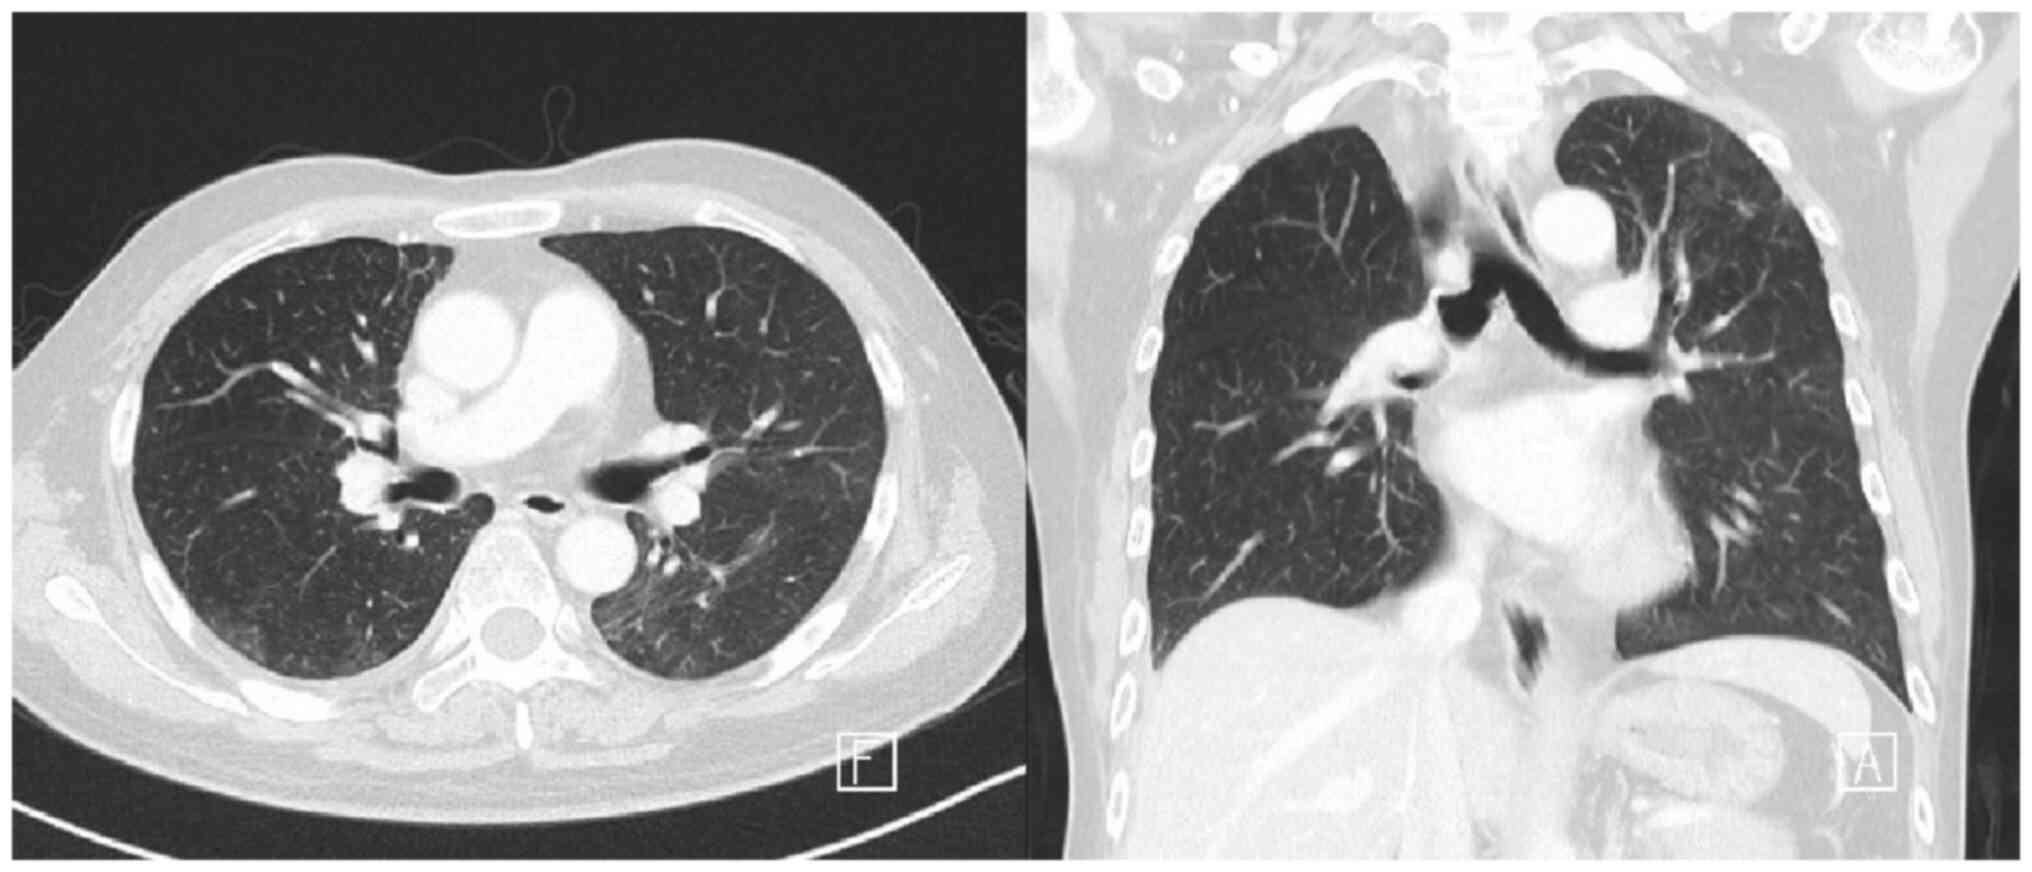

The patient was again admitted to hospital in January 2023 due to progressive dyspnea, and treatment with capmatinib was maintained up to January 2023. A chest X-ray showed bilateral infiltrations. Chest CT scan images showed extensive ground-glass opacity in both lungs and subpleural consolidation, which led to a suspected diagnosis of drug-induced ILD and pneumonia (Fig. 1). The patient was tested for influenza A and B, coronavirus disease 2019, and Legionella and Mycoplasma antibodies, which are potential causes of ILD and were common tests conducted in Taiwan in 2021; however, these tests were negative. Systemic steroids consisting of 120 mg methylprednisolone per day and antibiotics consisting of 750 mg levofloxacin per day were then prescribed and the patient's oxygenation status improved. The follow-up chest X-ray also showed improvement of the bilateral infiltrations. Antibiotics were discontinued and systemic steroids were gradually titrated until the patient was only receiving oral prednisolone. The follow-up chest CT images demonstrated marked regressive changes in the bilateral ground-glass opacity (Fig. 2). The patient was discharged after 14 days of treatment. Treatment with oral tepotinib, another type of MET inhibitor, was provided once daily [administered as two 225 mg tablets (450 mg)] for 21 days at 1 month post-discontinuation of capmatinib treatment. The patient undergoes monthly follow-up chest X-rays, with chest CT scans every 3 months. The last follow-up was in June 2023, and currently, there are no signs of ILD.

Figure 2.

Chest computed tomography images. Marked regressive changes were observed in the bilateral ground-glass opacity previously exhibited by the patient (arrows).